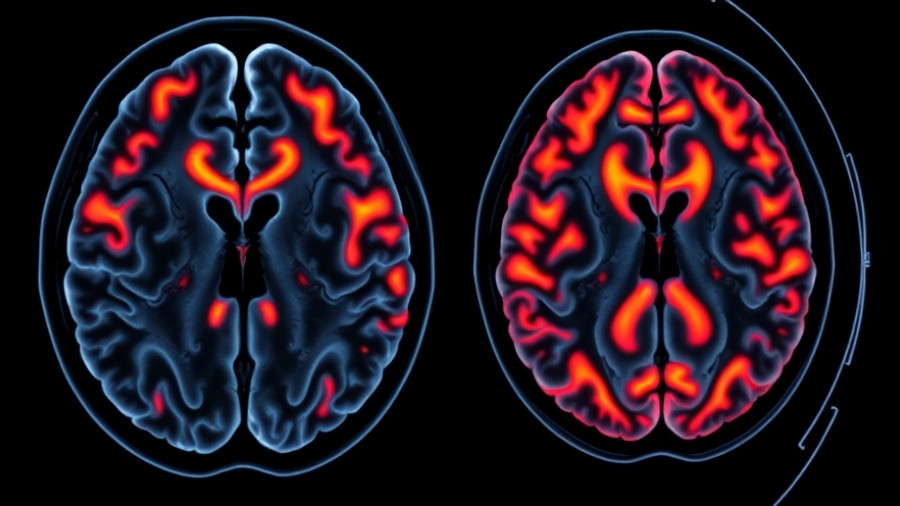

Tamaki and her team revealed that during deep sleep, the brain employs cerebrospinal fluid (CSF) to clear metabolic waste products that accumulate during wakefulness. Their study, published in the Proceedings of the National Academy of Sciences, utilized a novel sparse functional MRI technique to observe changes in CSF signals linked to slow brain waves that occur during deep, non-REM sleep. This groundbreaking approach allowed participants to reach deep sleep while undergoing brain scans, yielding insights that suggest that the dynamics of CSF flow might be integral for effective memory management.

The research uncovered that different sleep stages are associated with varying brain activity patterns and CSF signal changes. During deep sleep, the hippocampus and frontal cortex — areas responsible for learning and memory — are particularly active. This specific neuronal activity triggers a release of CSF that plays a role in 'cleaning' the brain. In contrast, during lighter sleep and REM stages, this process appears less efficient, inviting further inquiry into how enhancing deep sleep could optimize cognitive performance.